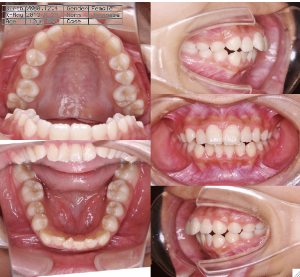

装置装着前

装置装着後

元の歯ならびの状態にもよりますが、通常約1年から2年ぐらいです。